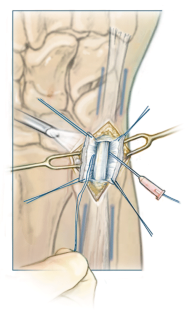

Operationstechnik

Minimal-invasive Naht des Discus triangularis an den Boden des sechsten Strecksehnenfachs unter arthroskopischer Sicht.

Surgical technique

Arthroscopically guided, minimally invasive suture of the TFCC to the base of the sixth extensor compartment.